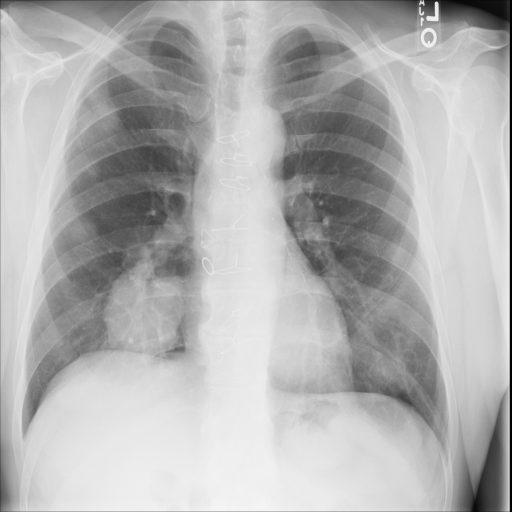

In Fig. 1, we show four ϵitalic-ϵ\epsilon-LDP-processed CXR images of clinical cases obtained with the image domain LDP, which directly imposes the Laplace mechanism on the input image, with different privacy budgets together with the original images. Fig. 2 shows four ϵitalic-ϵ\epsilon-LDP-processed CXR images of clinical cases obtained with DP-GLOW and different privacy budgets together with the original images. In case 1 for DP-GLOW, there is decreased permeability in the bilateral hilar regions. Although this hilar opacity tends to be preserved with a larger privacy budget, the entire image is degraded when the privacy budget becomes 101HWsuperscript101𝐻𝑊10^{1}\cdot H\cdot W. A similar tendency is observed in the images of all the four cases for DP-GLOW; for example, in case 4 with ϵ=101HWitalic-ϵsuperscript101𝐻𝑊\epsilon=10^{1}\cdot H\cdot W, the lung opacity suggesting pneumonia in the right lower lung field is well preserved, while the entire image is degraded.

7.2 Qualitative assessment of LDP-processed CXR images

Here, we assume two possible privacy leakage scenarios. To CXR images, we intentionally add features that can lead to the re-identification of the subject appearing in a CXR image. The first feature is an artificial block marker. The second feature is a rare anatomical abnormality known as situs inversus simulated by flipping a CXR image along the vertical axis. Figs. 3(a) and 3(c) show CXR images with the artificial block marker. Fig. 5(a) shows a flipped CXR image to represent a case of situs inversus. We applied DP-GLOW to these CXR images. In Figs. 3(b) and 3(d), the image domain LDP fails to obfuscate the artificial block marker with a moderate privacy budget. In contrast, in Figs. 4(b) and 4(d), DP-GLOW successfully obfuscated the artificial block marker with the moderate privacy budget. On the other hand, the anatomical shape of the chest and the abnormal opacity (hilar regions in the case 1) are preserved. In Fig. 5(b), we observed that the right edge of the heart does not become obfuscated with the image domain LDP. In contrast, in Fig. 6(b), we observed that the right edge of the heart becomes obfuscated and the heart appears at the center of the thoracic cage with DP-GLOW. However, DP-GLOW with this privacy budget is insufficient to almost completely erase the feature of situs inversus.

Table 3 shows the area under the curve (AUC) with different privacy budgets for ϵitalic-ϵ\epsilon-LDP-processed CXR images obtained with the image domain LDP and DP-GLOW.

For DP-GLOW, the AUCs for pneumonia detection significantly change from 0.539 to 0.807, while the privacy budget varies from 101HW(=2,621,440)10^{1}\cdot H\cdot W(=2,621,440) to \infty. This means that this range of the privacy budget is indeed meaningful whereas the privacy budget is very large compared with usual values of ϵitalic-ϵ\epsilon-LDP for scalar quantities. This finding implies that we must normalize the privacy budget so that we can consistently handle ϵitalic-ϵ\epsilon-LDP for vector quantities. To normalize the budget, we compute the privacy budgets per image pixel. To this end, we intentionally indicated the privacy budget to have a common factor HW𝐻𝑊H\cdot W. Therefore, the actual privacy budgets per image pixel in this study are from 101superscript10110^{1} to \infty, which are not much larger than commonly accepted privacy budgets.

Most of the approximate forms in CXR images are preserved and privacy is not protected with the image domain LDP. On the other hand, given a low privacy budget, DP-GLOW deforms the image so much that individuals cannot be identified. However, the AUCs for pneumonia detection are similar with the low privacy budget between DP-GLOW and the image domain LDP.